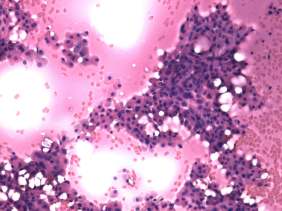

Cytological picture: there was diffuse colloid precipitate in the background. Beside compact clusters of follicular cells many isolated follicular cells were found. Thyrocytes partly exhibited oxyphilic metaplasia, but did not contain prominent nucleoli.

Cytological diagnosis: benign colloid goiter with oxyphilic metaplasia.